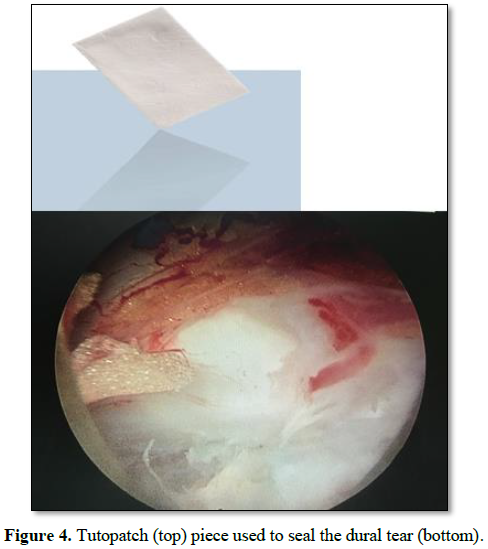

A 45 years old male patient presented

with a large, left-sided, L5-S1 disc herniation associated with bilateral pars

defect and low grade spondylolisthesis resulting in severe radical pain in the

left leg that failed to respond to conservative treatment (Figure 1). Dynamic X-rays of the lumbar spine did not show significant

movement of L5 over S1 (Figure 2).